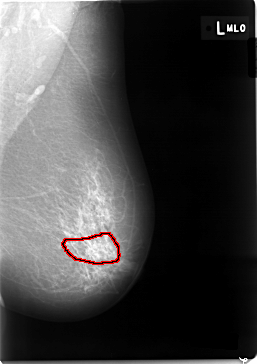

FILE: C_0002_1.LEFT_MLO.OVERLAY

TOTAL_ABNORMALITIES 1

ABNORMALITY 1

LESION_TYPE CALCIFICATION TYPE PLEOMORPHIC DISTRIBUTION SEGMENTAL

ASSESSMENT 4

SUBTLETY 1

PATHOLOGY MALIGNANT

TOTAL_OUTLINES 1

BOUNDARY